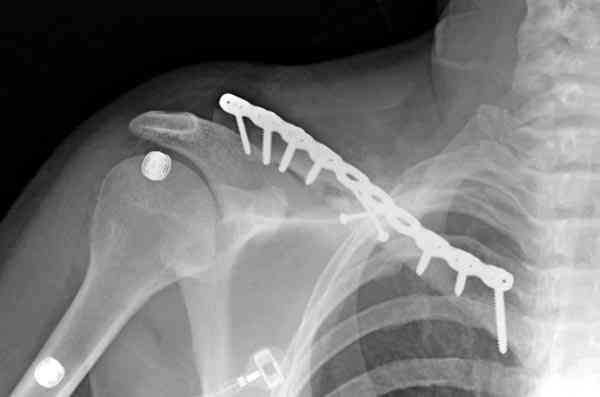

Преимуществами оперативного лечения (фиксация пластиной) является более низкий риск несращения и неправильного сращения, лучший функциональный результат к 1 году. Отрицательный момент - более

длительный период восстановления трудоспособности, необходимость в повторных операциях по удалению железа. С другой строны, большинство неправильно сросшихся переломов асимптомны, дискомфорт в области плеча, надплечья может возникать при укорочении более 1,5- 2 см, кроме того, отсроченные вмешательства при признаках несращения приводят к такому же функциональному результату, что и вмешательства в ранние сроки.

Мне представляется, что консервативное лечение предпочтительнее, за исключением случаев косметического дефекта, угрозы прободения отломком кожи, учитывая, кончено, требования пациента

При чем западные мсследования касаются большей частью сравнения остеосинтеза пластиной с консервативным лечением. У нас же в стране каждый оперирует по собственному разумению : пластинами, различными стержнями, спицами (что кстати и случилось у этого пациента)и т.д. с совершенно непрогонозируемым результатом